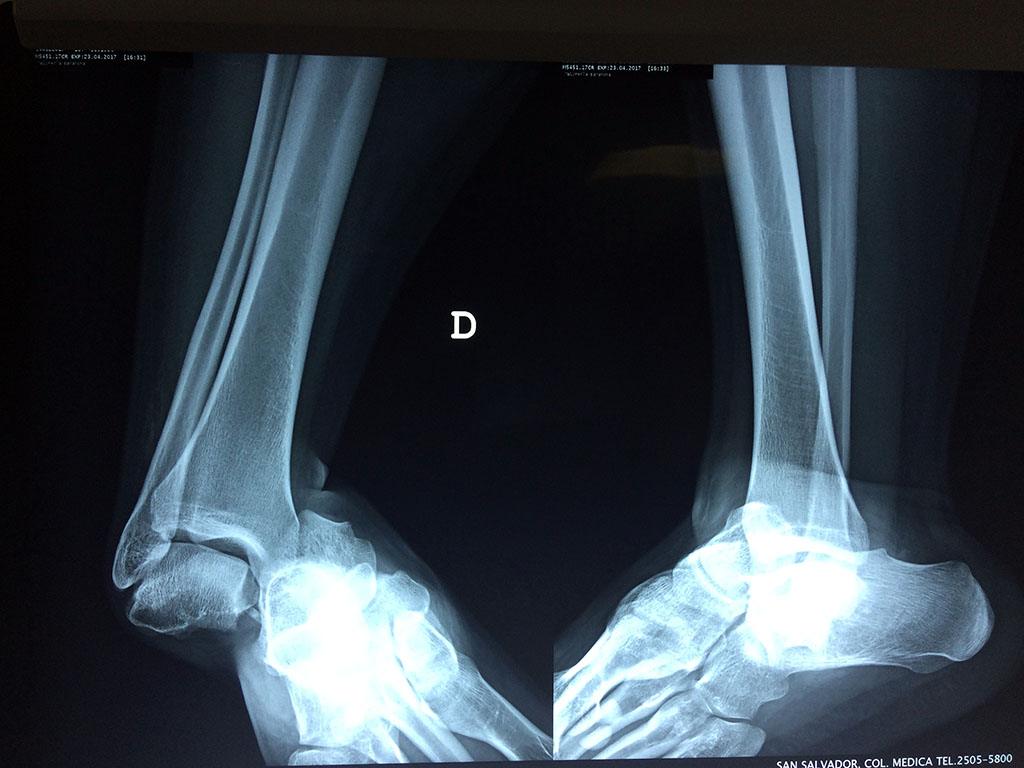

Algunas fracturas de tobillo pueden requerir cirugía si:

- Los extremos de los huesos están desalineados entre sí (desplazados).

- La fractura se extiende hasta la articulación del tobillo (fractura intra-articular).

- El médico cree que sus huesos probablemente no sanen apropiadamente sin cirugía.

- El médico considera que la cirugía puede permitirle una recuperación más rápida y confiable.